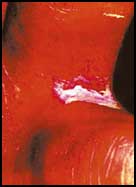

داء السكري وعلاقته بالقدمين

أن تأثير داء السكري على القدمين يضعف مقاومتها للجروح والقروح بسبب قصور الدورة الدموية في الأطراف وفي درجة الاحساس، لذا تأتي أهمية العناية بالقدمين بال.........